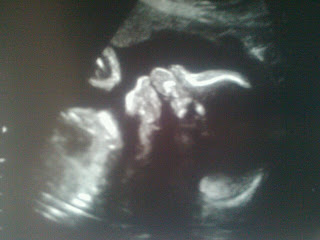

This is my favorite from this week - he's sucking his thumb sideways!!

Some pictures from this week's ultrasound (sorry they're dark): As a side note, whenever Nate comes home from work, he sits in the right-hand corner of the couch and props his feet on the bottom shelf of the coffee table: left heel on the ledge and right heel on the ankle of his left... exactly the way our little man had his feet positioned at the ultrasound today!